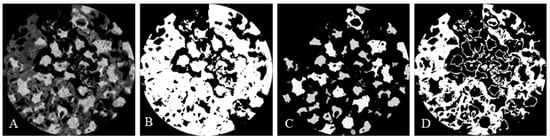

3.1. Morphology and Composition Analysis

3.3.1. Micro-CT Measurement